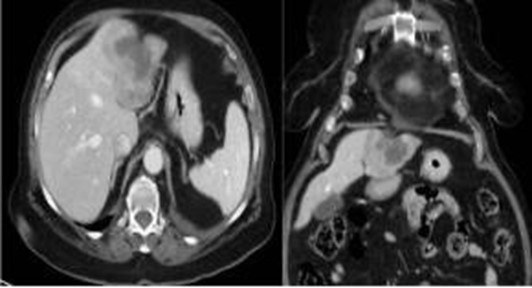

El CHC presenta una vascularización predominantemente arterial (por neovascularización) a medida que avanza el proceso de hepatocarcinogénesis, a diferencia del parénquima hepático, en donde la vascularización es mixta: arterial y portal. Este patrón característico, favorecido por la alta probabilidad del CHC en pacientes con hepatopatía crónica, ha mostrado una especificidad próxima al 100% para el diagnóstico de CHC. No obstante, este patrón vascular está penalizado por una sensibilidad del 60%-70% en lesiones de pequeño tamaño, y se ha descrito que alrededor de un 15% delos CHC de pequeño tamaño son hipovasculares al no haber desarrollado aún su neovascularización, sin que ello indique que estas lesiones tengan un comportamiento menos agresivo.(18-21) No obstante, en ocasiones el carcinoma hepatocelular puede ser hipovascular y no mostrar reforzamiento intenso en la fase arterial, siendo en estos casos muy importantes las fases venosas portal y venosa tardía, en donde la lesión permanece hipodensa o incluso puede presentar un comportamiento atípico con importante reforzamiento en la fase arterial y ausencia de lavado tardío (Anexos 10 y 11).

Hepatocarcinoma fibrolamelar

El carcinoma fibromelar hepatocelular es poco frecuente y representa menos de 1% de todos los casos. Se presenta principalmente en adolescentes y adultos jóvenes como una masa tumoral hepática única, con frecuencia de gran tamaño, sin asociación con cirrosis y rodeada de una cápsula fibrosa. En la tomografía multicorte, sin contraste, se observan tumores hipodensos heterogéneos con una cicatriz central muy hipodensa. También puede haber áreas de necrosis y calcificaciones. Son lesiones hipervasculares con captación intensa pero heterogénea (Anexo 15) del medio de contraste en fase arterial, la captación en fase portal y de equilibrio son variables y la cicatriz central, los septos y la cápsula del tumor son hiperdensos en fase tardía, incluyendo en los estudios de RM.(18-19)